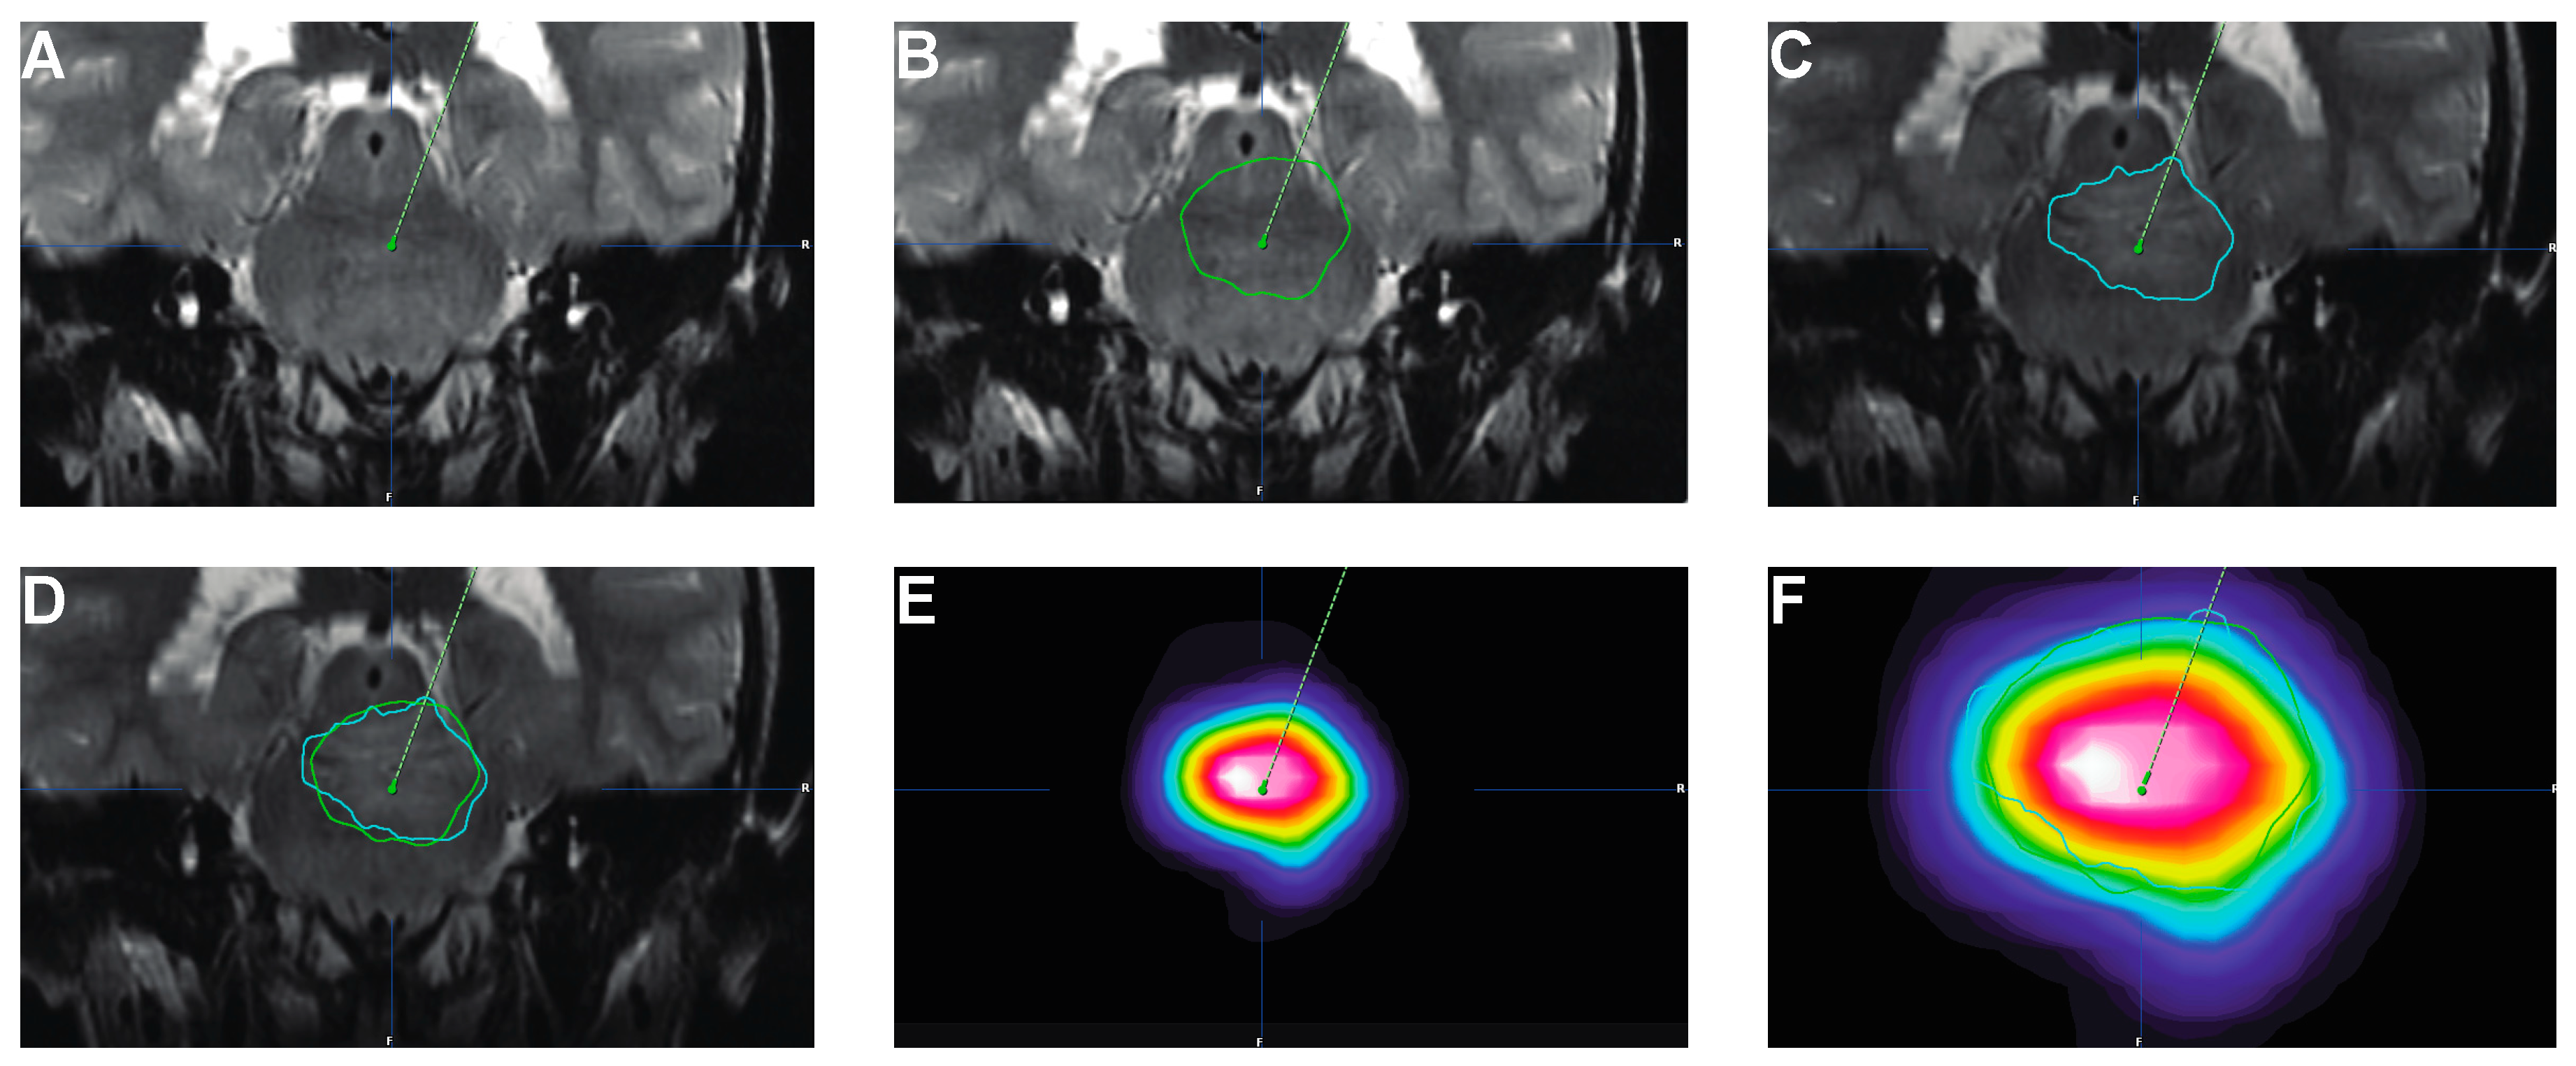

- Singh, R.; Zhou, Z.; Tisnado, J.; Haque, S.; Peck, K.K.; Young, R.J.; Tsiouris, A.J.; Thakur, S.B.; Souweidane, M.M. A novel magnetic resonance imaging segmentation technique for determining diffuse intrinsic pontine glioma tumor volume. J. Neurosurg. Pediatr. 2016, 18, 565–572. [Google Scholar] [CrossRef]